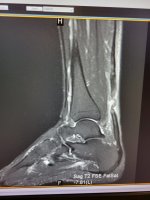

This one is a Doozie. 2 years walking in reed canary grass along a creek on a WPA in south central SD. Step into a hole if which my entire size 9 boot goes in and I fall backwards and hear a SNAP. Incredible pain. Laying in the grass I realize my foot/calf muscle no longer function. I diagnose myself with a ruptured Achilles. 1/4 mile walk to truck over a fence, load the dog and drive 50 miles to hospital. ER dr thinks i have a ruptures Achilles, but can't get a MRI for 2 days. Dr wraps it and gives me crutches. Head back to air bnb that evening. Leave for sioux falls and seen by a orthopedic leg/foot specialist. Confirms my diagnoses. This where it gets better, dr informs me he can work me into surgery the following day. HOWEVER my HMO insurance denies me surgery since I'm out of network and the injury is not life threatening. I appeal, they still deny the surgery. Imagine that in October 2022. Drive home the next day by myself with 3 dogs in a orthopedic boot. A week later I final get surgery to tie Achilles together. I was 5" apart. 3 months in a cast, no walking, missed the entire upland season. The mental duress of not hunting the rest of the year was far worse than the pain/rehabilitation.